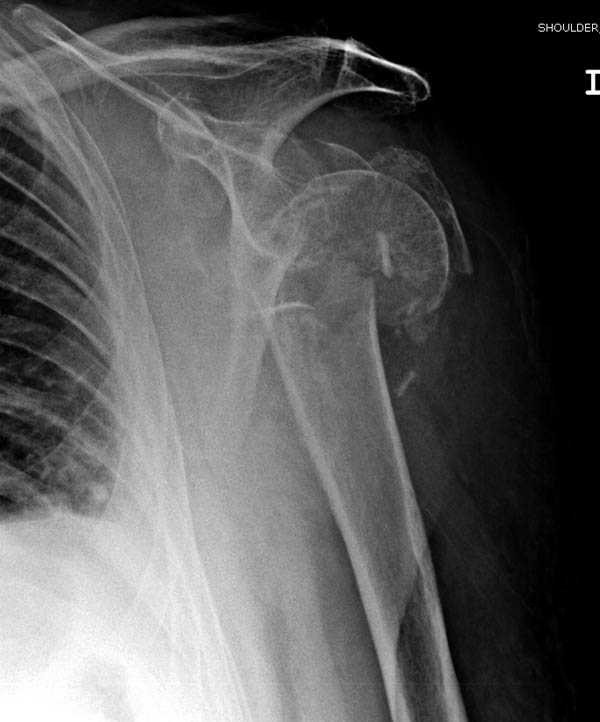

Пациентка Б.1953 г.р., врач-терапевт. Травма 27.11.08г. Падение с высоты роста. Выявлен закрытый не осложненный оскольчатый перелом хирургической шейки левого плеча со смещением. 02.12.08г. оперирована. Выполнена открытая репозиция и остеосинтез пластиной LCP Деост с дополнительной фиксацией отдельно лежащего фрагмента винтом. Послеоперационный период протекал без особенностей, заживление раны первичным натяжением. Швы сняты через 10 дней. Иммобилизация левой верхней конечности клиновидной подушкой 4 недели. По окончании срока – рентген-контроль и умеренная разработка плечевого сустава. В течении месяца функция левого плечевого сустава восстановилась удовлетворительно: поднятие руки до 110 гр., отведение - 90 гр. и до 110 гр. отведение с лопаткой. Отведение руки назад – 20 гр. Наружная и внутренняя ротация – 20 гр. Пациентка по настоянию самостоятельно вышла на работу. 27.03.09 при контрольном осмотре жалоб не предъявляет, болевой синдром в левом плечевом суставе отсутствует. Отведение плеча активно до 90 гр, пассивно с лопаткой до 110 гр., поднятие – 110 гр, отведение назад 20 гр, наружная и внутренняя ротация по 20 гр. На контрольных рентгенограммах отмечается смещение металлоконструкции, ротация головки плеча с приведением дистального отломка на 13 гр. и смещением к зади на 30 гр. Рентгенограммы прилагаются. Ваш взгляд на дальнейшую тактику лечения пациентки?

Уважаемый Евгений, похоже, что первый и второй Р-снимки выполнены несколько в разных положениях(ротация) плечевой кости, в связи с этим создается впечатление смещения пластины. Остеосинтез выполнен при угловом смещении отломков.Таковым и остался. Данная ситуация была бы очевидна гораздо раньше, если бы при контрольной Р-графии были выполнены снимки в 2-х проекциях.(Не в обиду, сам иногда выполняю только один).

Рентгенограммы действительно с дефектом укладки, но интраоперационная репозиция, можете поверить, была удовлетворительная как в акcиальной, так и в сагиттальной плоскостях. Интраоперационная рентгенограмма прилагается, хотя укладка тоже на ахти. По тактике - разделяю Ваше мнение об отсутствии необходимости реостеосинтеза, а тем более об эндопротезировании, хотя это все было предложено пациентке ведущими ортопедами-травматологами России.

Здесь пример открытой репозиции 57 летнего с переломом плеча (1,2) смещение обнаружено на интероперационном снимке. При нормальной прямой проекция (3) угловое смещение обнаружили в аксиальной проекции (4)